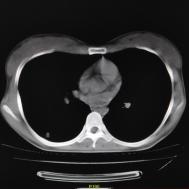

[影像描述]

两肺内及胸膜下多发斑片状高密度影,部分病灶密度较淡,部分实变,边缘可见渗出改变。